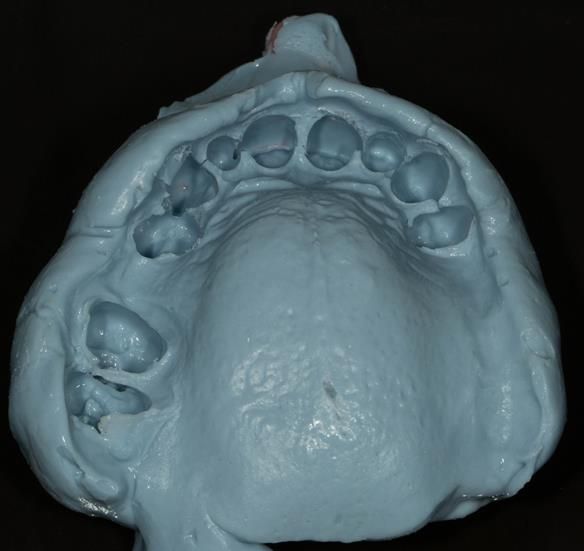

This newsletter describes in step by step detail Angela's transition through immediate partial dentures to crown supported definitive metal based dentures.

The clinical situation and treatment process is shown in detail below with photographs. I (Finlay Sutton) provided the clinical work and Rowan Garstang provided the technical work.